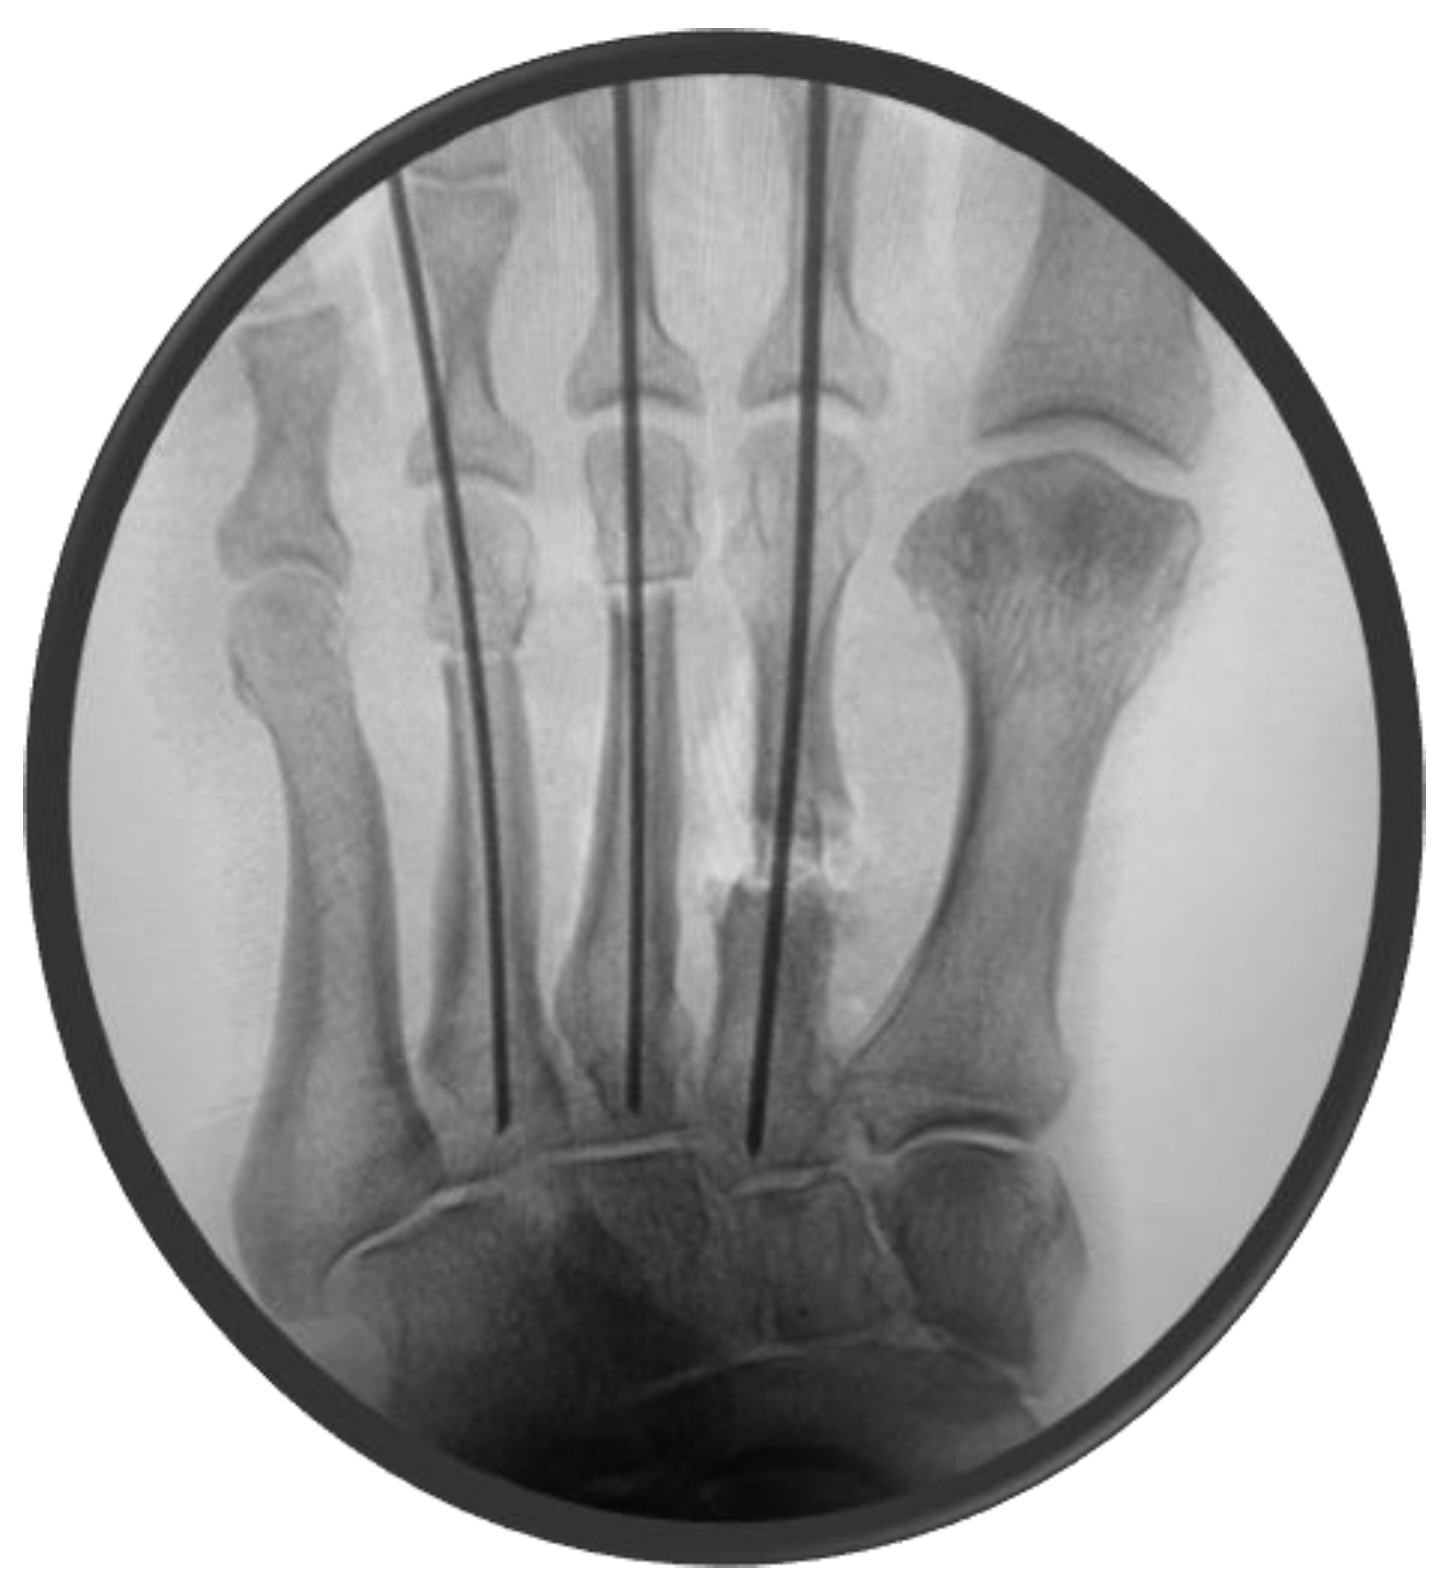

The second metatarsal was synthesized using a 1.6 mm K-wire, whereas the third and fourth metatarsals were stabilized using 1.4 mm K-wires emerging from the base of the apex of the second, third, and fourth rays under fluoroscopic control (Figure 3).

Figure 3. Fluoroscopic control post-synthesis using 1.4 and 1.6 K-wires.